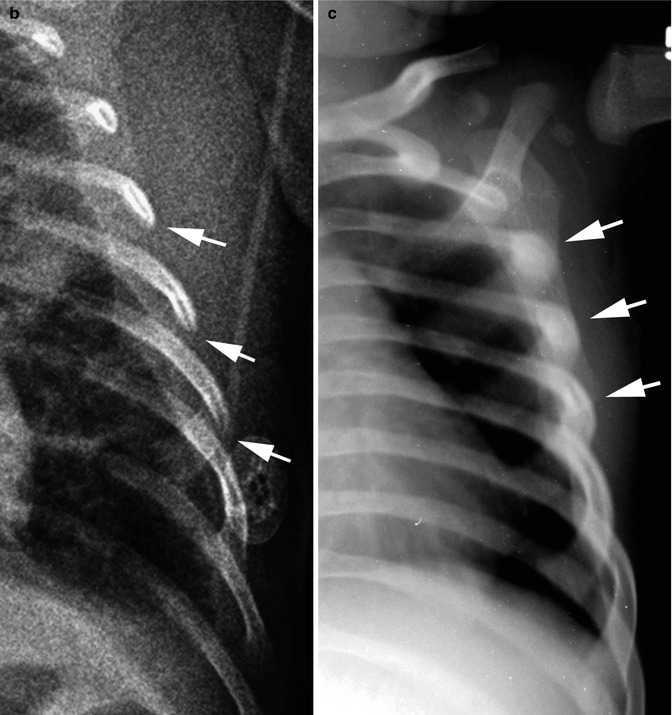

Медицина и диагностика: Аномалии ребер на рентгене